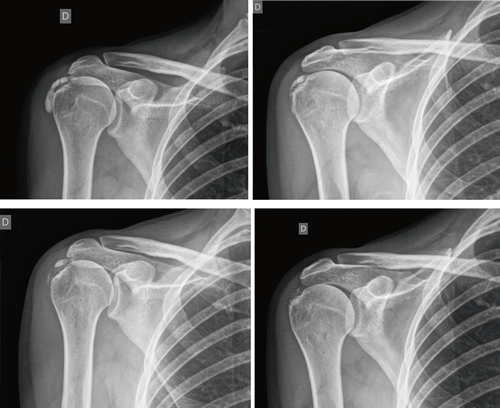

The average number of sessions in our series was 20. The criteria for continuing or stopping treatment was the radiological and clinical evolution (Figures 4 and 5). The interventions were performed up to a maximum of 40 sessions. Perrón treated patients for 9 sessions (3 weekly sessions for 3 weeks) (14). Leduc treated with 10 sessions (3 per week for the first two weeks; then one weekly for 4 weeks) (15). Rioja-Toro treated patients for 40 sessions (5 times per week) and evaluated them at 20 and 40 sessions (3). Chico-Álvarez treated patients between 15 and 30 sessions depending on the radiological evolution (5 times per week) (1).

Fig. 4. 47-year-old female patient with formative right supraspinatus calcific tendinitis who, after 30 sessions of iontophoresis, decreased pain measured by VAS from 6/10 to 3/10 and calcification from 38 mm to 8 mm (assessments at onse and at 10, 20 and 30 sessions, respectively).

Fig. 5. A 44-year-old female patient, with calcific tendinitis of the left supraspinatus, of the resorptive type, who after 20 sessions of iontophoresis decreased pain measured by VAS from 10/10 to 4/10, and calcification from 22 mm to 0 mm (complete disappearance).